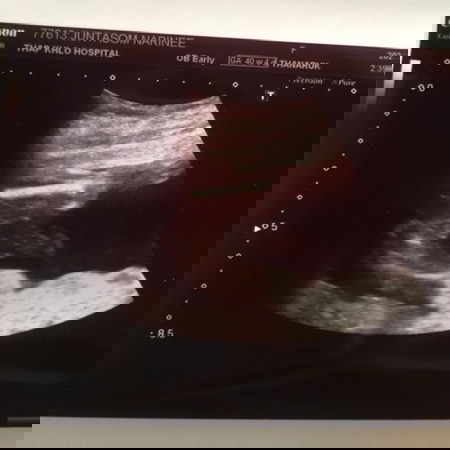

เเล้วเเบบนี้ผู้หญิงหรือผู้ชายคะเเม่ๆหทอยอกผู้หญิงค่ะเเต่เเม่ไม่ค่อยเเน่ใจเลยมาไห้เเม่ๆทายจ้า

ชัดขนาดนี้ ชายจ้าา เหมือนบ้านนี้เลยค่ะแม่ ไข่และปิก้าจู ชัดมาก555 ตรวจนิฟตี้ผลก็ยืนยันชายจ้า

ผู้หญิงหรือผู้ชายค่ะ ฝากแม่ๆช่วยดูให้หน่อยค่ะ แม่บ้านนี้ดูไม่เป็นค่ะ ขอบคุณคะ🙏🏻🥰🥰

เหมือนเห็นจู๋น้องเลย แต่หมอว่าเป็นผู้หญิง แม่ๆว่าเห็นเป็นผู้ชายไหมคะ

ผู้หญิง หรือ ผู้ชายคะ ฝากแม่ๆช่วยดูให้หน่อยนะคะ ขอบคุณค่ะ🥰🙏🏻